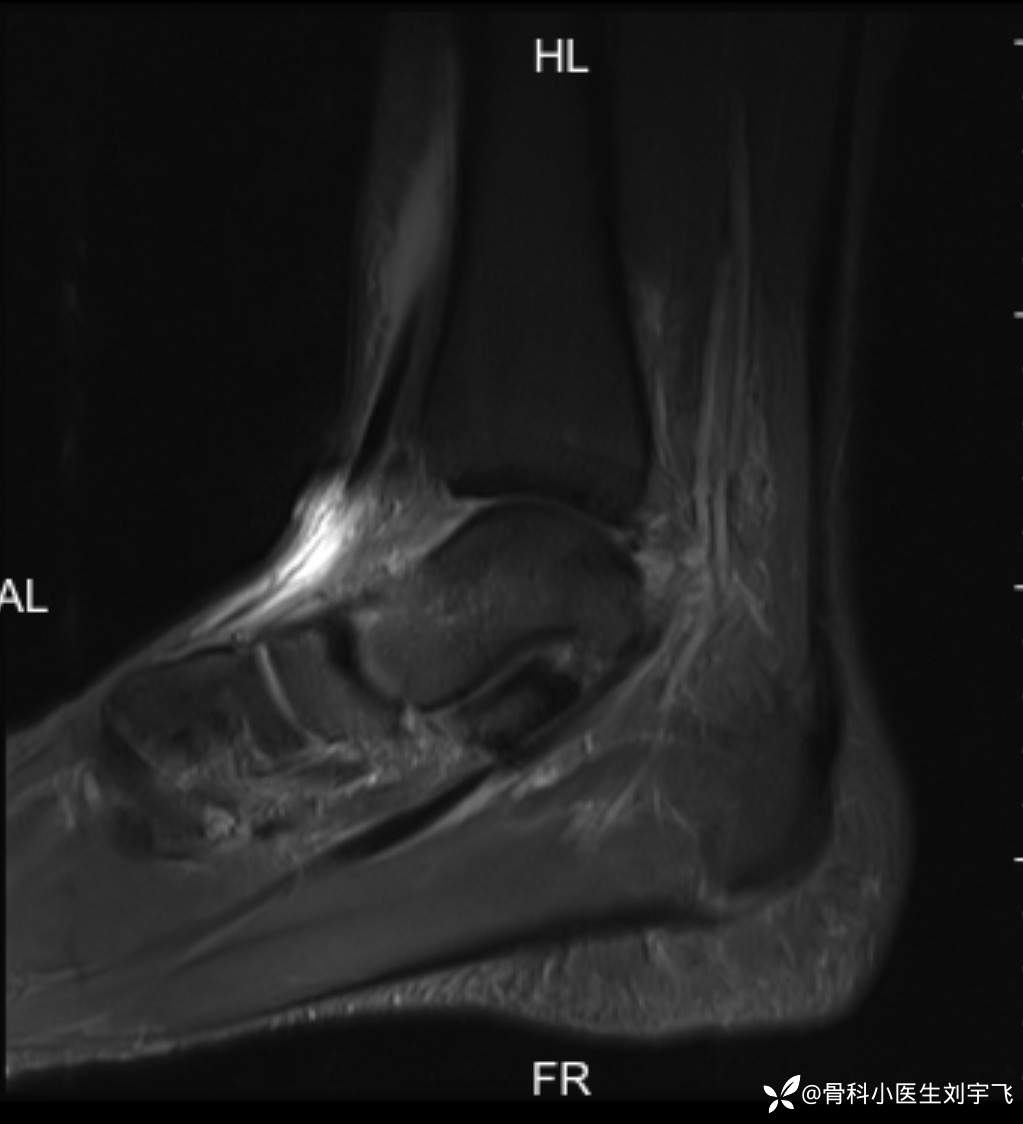

踝关节扭伤后,内外侧疼的很厉害,大家看一下这个核磁

辅助检查:MRI X线

临床诊断:距腓前韧带撕裂 三角韧带损伤、胫骨前肌腱损伤?